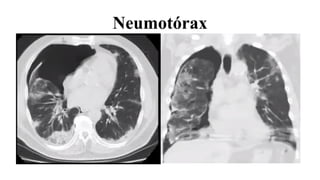

●Neumotórax

Neumotórax